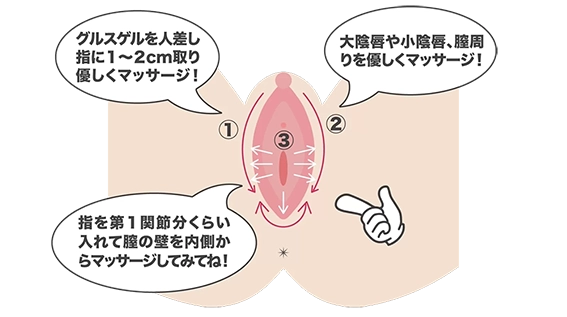

当初、男性向けの製品として製薬会社と協議を進めていましたが、調査を進める中で女性にも多くの健康課題があることを認識しました。世界的に女性の社会進出が進む中、日本が他国に比べて技術の導入に遅れを取っている現状があります。最近では『フェムケア』という言葉も認知され始めましたが、まだまだ理解されていない状況です。女性の健康と活躍を支援したいという思いから、男性だけでなく女性も対象とした商品開発に方針を転換しました。一般に流通している製品の中には、心臓への負担やその他の懸念がある製品もありますが、それらを軽減し安全に使用できる製品を提供したいと考えています。現在でも、不安を感じながら製品を使用されている方が多くいらっしゃると思います。私たちは、より気軽で安心して使用できる製品を開発し、皆様の健康と幸福に貢献したいと願っています。